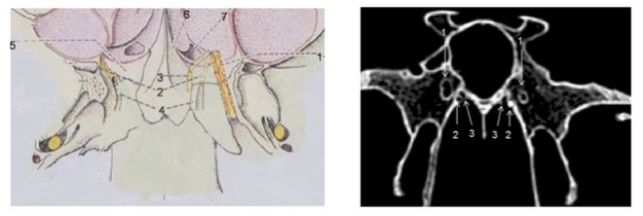

左图为一例新鲜尸头标本的左侧腭鞘管解剖。右图为该患者二次鼻内镜手术时所见(右侧),磨除腭骨蝶突后见出血来源于咽动脉,予以双极电凝烧灼并离断,同时可见初次手术时烧灼离断的蝶腭动脉。S 鼻中隔,SS 蝶窦,NPh 鼻咽,SPA 蝶腭动脉,PhA 咽动脉,sb-SPA 鼻中隔后动脉,nb-SPA 蝶腭动脉的鼻腔外侧壁分支,VC 翼管。

左侧上颌动脉远端分支的示意图。SS 蝶窦,ET 咽鼓管,ION 眶下神经,ICA 颈内动脉,IMA 上颌动脉,DPA 腭降动脉,VA 翼管动脉,PhA 咽动脉,sb-SPA 鼻中隔后动脉,nb-SPA 蝶腭动脉的鼻腔外侧壁分支。